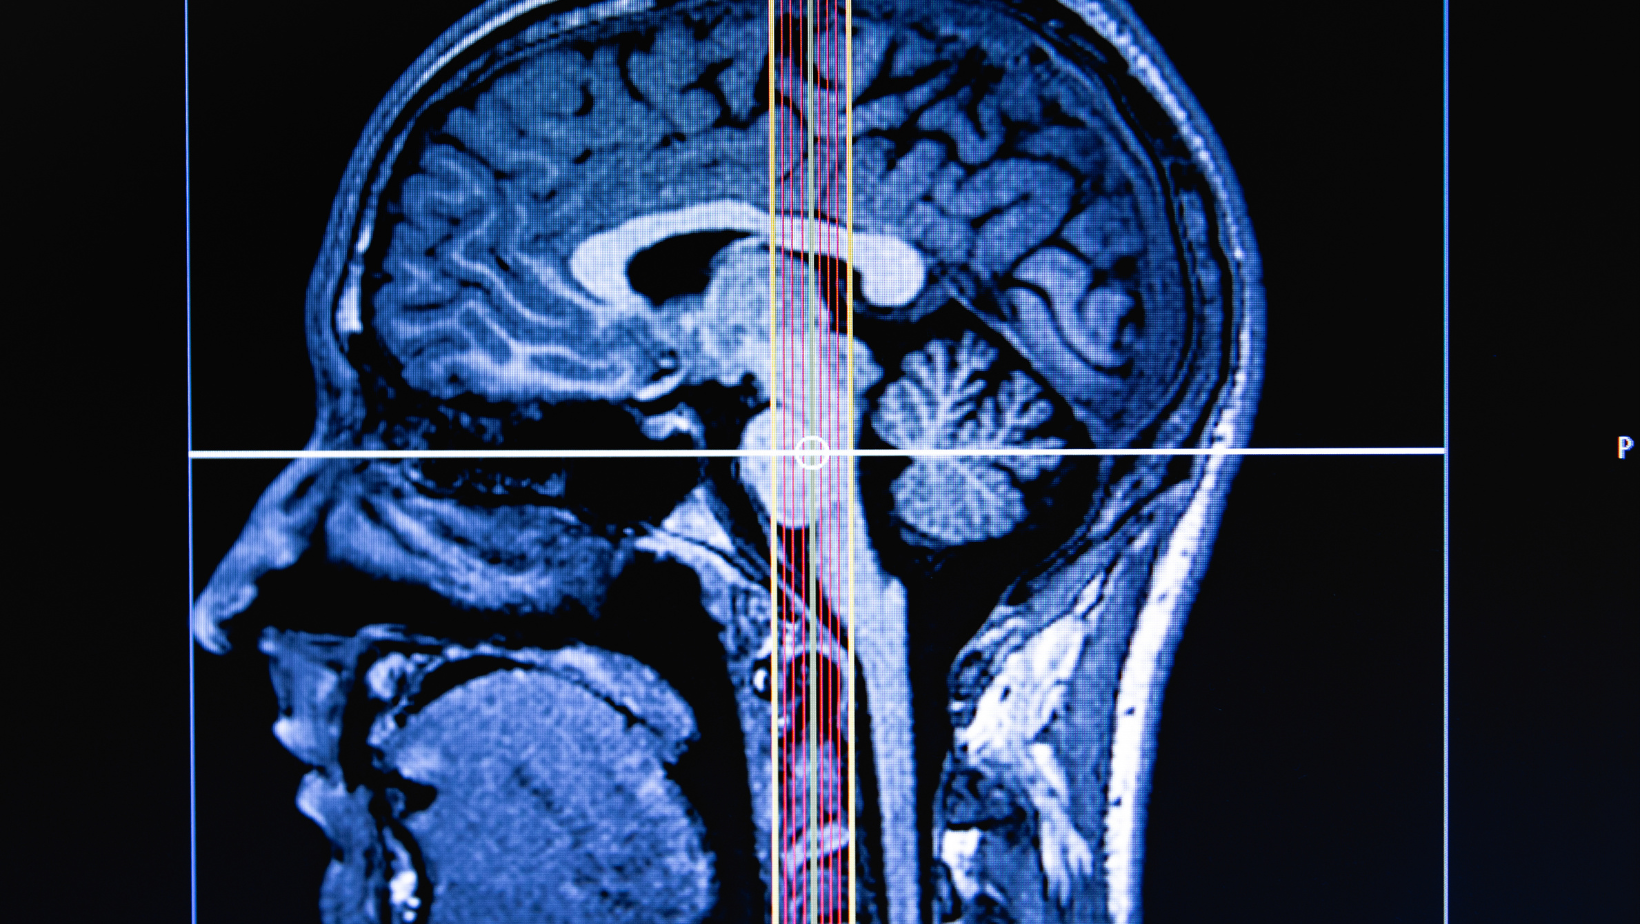

A diferencia de un análisis de sangre, medir el glutatión cerebral requiere tecnología avanzada de imagen (Espectroscopia por RM). Son pruebas que se utilizan principalmente en investigación científica para entender mejor cómo el estrés oxidativo afecta al cerebro humano.